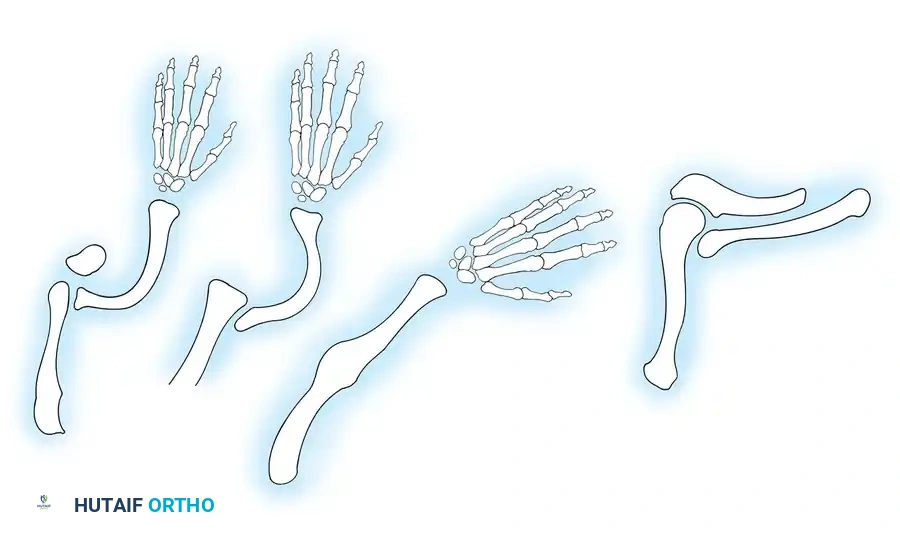

Transverse deficiencies represent a failure of formation (arrest of development) characterized by the complete absence of parts distal to a specific point on the upper extremity. This produces an amputation-like stump. Classification is strictly anatomical, naming the level at which the remaining stump terminates (e.g., proximal third forearm deficiency).

Wynne-Davies and Lamb reported the incidence of transverse deficiencies to be approximately 6.8 per 10,000 live births. The vast majority (98%) are unilateral, with the most common anatomical level being the upper third of the forearm. There is no established sex predilection.

Hypoplasia of the more proximal musculature is a key clinical finding that helps differentiate true transverse deficiencies from amputations caused by congenital constriction band syndrome (amniotic band sequence). In the most common presentation—the upper forearm amputation—the forearm is usually no more than 7 cm long at birth and will reach a maximum length of approximately 10 cm by skeletal maturity.